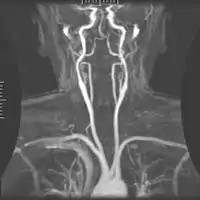

| Артерії шиї. На малюнку, загальна сонна артерія позначена як Common carotid поділяється на внутрішню та зовнішню сонні артерії. | |